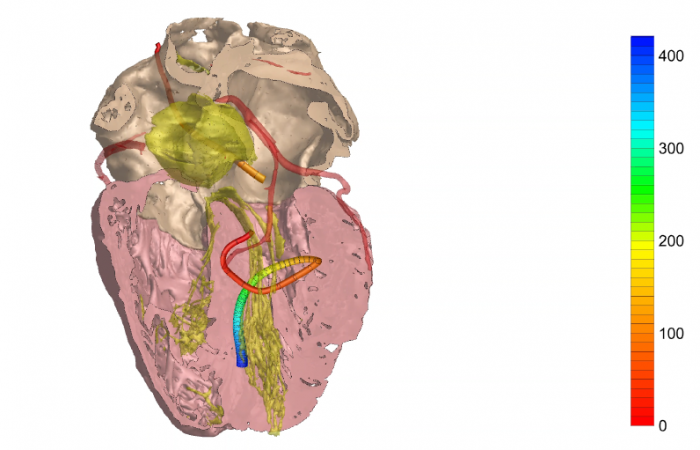

Pracownia Funkcjonalnego i Wirtualnego Medycznego Obrazowania 3D (Pracownia 3D-FM) funkcjonuje w strukturze Zakładu Diagnostyki Obrazowej Szpitala Uniwersyteckiego w Krakowie pod kierownictwem Prof. dr hab. Tadeusza Popieli. Jej celem jest opracowanie i wdrożenie innowacyjnych metod przetwarzania oraz analizy sygnałów i obrazów medycznych, w tym wykorzystanie technologii rzeczywistości wirtualnej oraz metod obrazowania funkcjonalnego. Rozwiązania te wspierają przedoperacyjne planowanie, monitorowanie procedur medycznych oraz wzbogacają proces diagnostyczny o nowe formy wizualizacji danych medycznych.

Pracownia 3D-FM zajmuje się m.in. następującymi obszarami:

- Tworzeniem modeli 3D do celów przedoperacyjnego planowania oraz wizualizacji diagnostycznej.

- Obrazowanie Medyczne 3D

- Segmentacja i analiza danych DICOM

- Rekonstrukcja danych medycznych

- Technologie immersyjne (mieszana, rozszerzona i wirtualna rzeczywistość)

- Obrazowanie funkcjonalne

- Elektrokardiograficzne obrazowanie 3D (ECGI)

- Modelowanie fizjologiczne

- Analiza sygnałów czasowych, w tym EKG

Pracownia Funkcjonalnego i Wirtualnego Medycznego Obrazowania 3D łączy nowoczesne technologie z praktycznym zastosowaniem w diagnostyce i terapii. Dzięki interdyscyplinarnej współpracy oraz zaawansowanym narzędziom badawczym dążymy do podnoszenia standardów opieki medycznej w Szpitalu Uniwersyteckim w Krakowie.